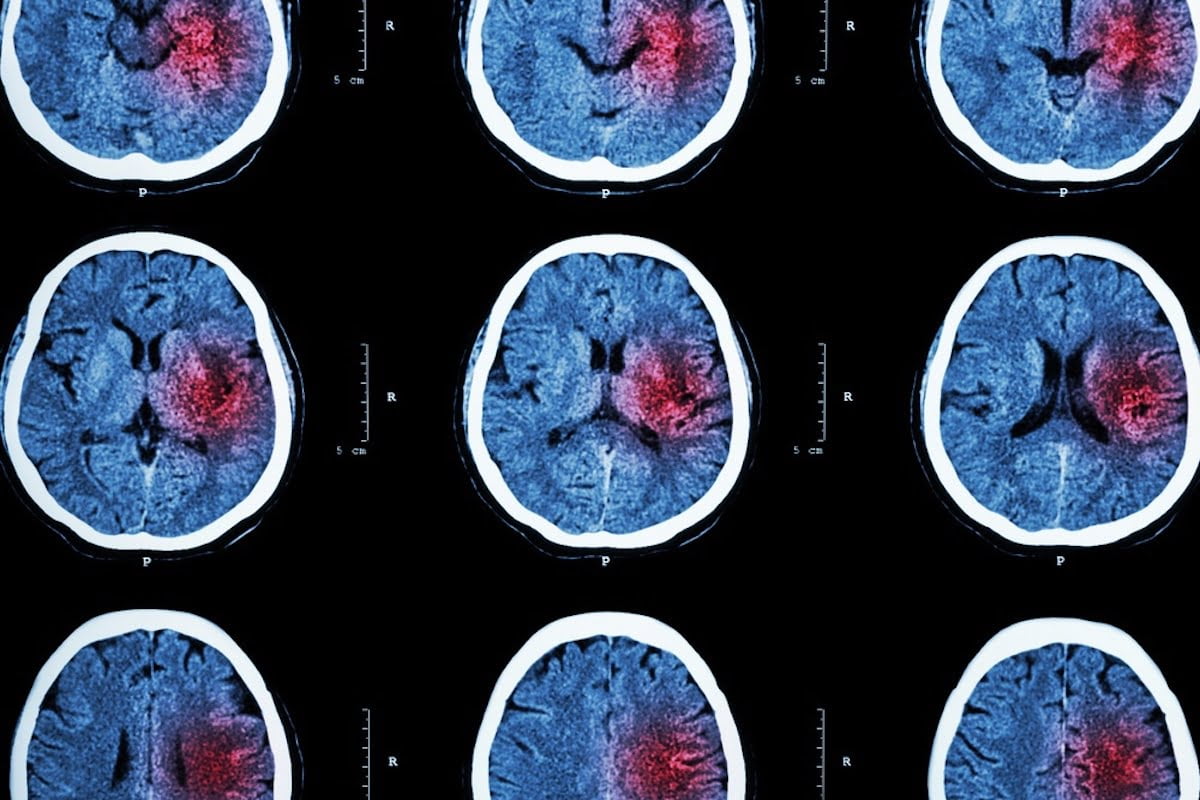

Esmae Hodgetts, una giovane e sana infermiera dentale di 20 anni, ha vissuto un’esperienza traumatica quando è stata colpita da un ictus. Nel raccontare la sua storia, Esmae ha voluto mettere in luce l’importanza di non ignorare i sintomi apparentemente banali, poiché possono essere il campanello d’allarme di un problema serio come l’ictus. Con il desiderio di sensibilizzare altri ventenni riguardo a questa possibilità, Esmae sottolinea che l’ictus può colpire chiunque, indipendentemente dall’età.

Gli stessi medici sono stati sorpresi dalla diagnosi di ictus su Esmae, poiché la sua coordinazione e il suo modo di parlare sembravano normali. La giovane è stata colpita da un ictus per quasi due giorni senza che venissero riconosciuti i sintomi tipici della condizione. Solo grazie ai risultati di una risonanza magnetica è stata possibile la diagnosi corretta.